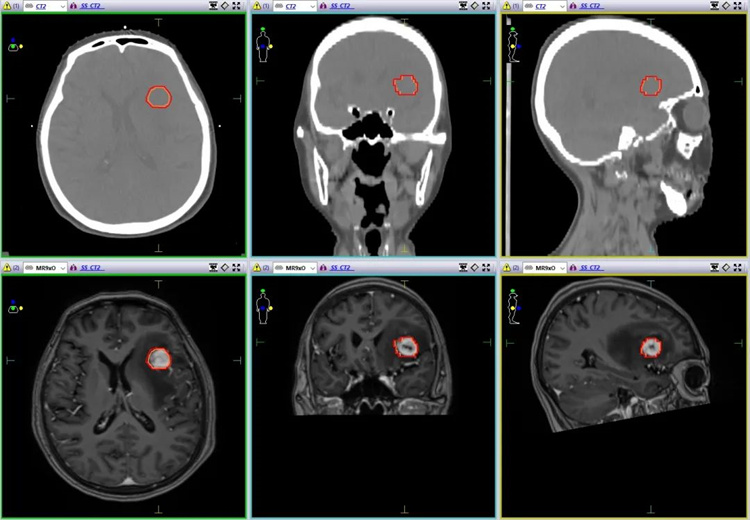

患者何某某,女性,70岁,2022年初在外院诊断为右肺上叶腺鳞癌并行手术切除,于今年7月出现头晕、头痛、恶心、呕吐,入巴中市中医院行头颅增强MRI提示:左侧额叶转移病灶,大小约1.7cm*2.0cm。

患者一般情况较好,PS评分1分,无明显放疗禁忌症,根据非小细胞肺癌CSCO指南(2022),经肿瘤放疗中心医师、物理师讨论后提出针对脑转移灶采用SBRT技术,处方剂量:5Gy/fx*7f。

图像融合下精准勾画靶区

物理师根据放疗处方采用容积旋转调强放疗(VMAT)技术,医生按照SBRT剂量指标进行评估,符合剂量学要求。正式实施前,首先进行了加速器性能检测,保证加速器剂量和影像验证系统的精度,同时对放疗计划进行了模体剂量验证,测试了端对端传输的准确性。

每次治疗前通过锥形束CT(Cone beam CT,CBCT)进行影像验证,医师、物理师、技师共同参与摆位、验证及治疗,肿瘤位置误差被控制在1mm以内,在肿瘤受到高剂量照射的同时,更好的保护了周围正常脑组织。